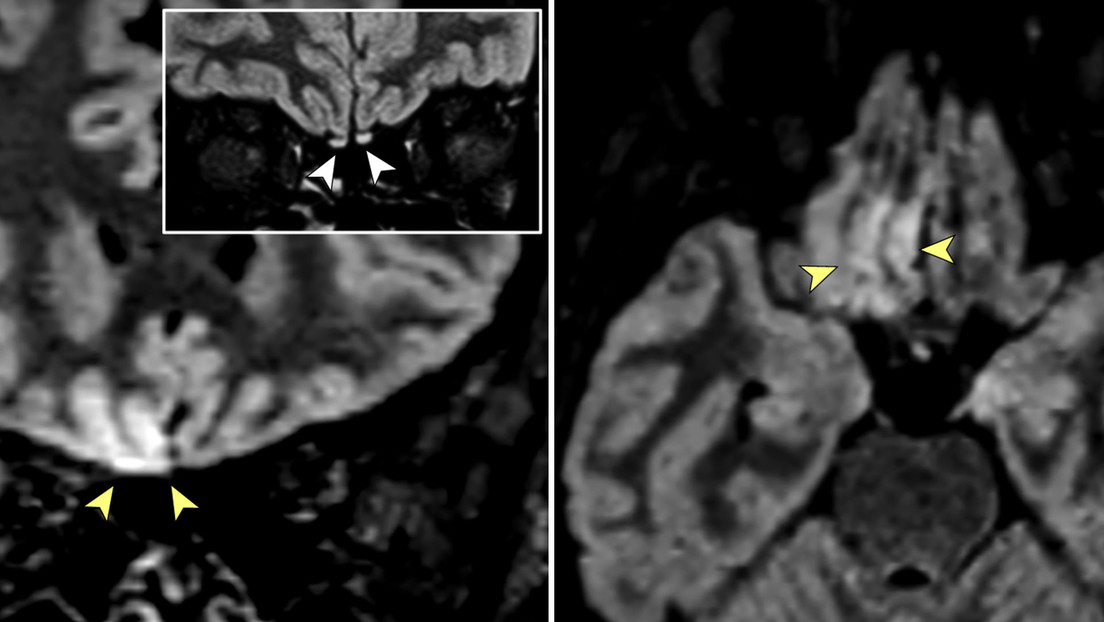

Imágenes de resonancia magnética de una italiana diagnosticada con el covid-19 y que desarrolló la pérdida del olfato, entre otros síntimas, mostraron signos de "invasión cerebral viral", revela un estudio publicado en la revista JAMA Neurology.

La mujer, de 25 años, que dio positivo por el coronavirus, tenía síntomas leves de la enfermedad, pero la resonancia magnética reveló una inflamación en su bulbo olfatorio, la estructura neural del cerebro involucrada en el sentido del olfato, que era "sugestivo de la infección viral".

"Hasta donde sabemos, este es el primer reporte de una participación del cerebro humano 'in vivo' en un paciente con covid-19 que muestra una alteración de la señal compatible con la invasión cerebral viral en una región [...] cortical que está asociada con el olfato", señalaron los autores del informe.

"Según los hallazgos de la resonancia magnética, incluidos los ligeros cambios en el bulbo olfativo, podemos especular que el SARS-CoV-2 podría invadir el cerebro a través de la vía olfatoria y causar una disfunción olfativa de origen neurosensorial", concluyeron los investigadores, quienes subrayaron la necesidad de realizar más pruebas para confirmar su hallazgo.